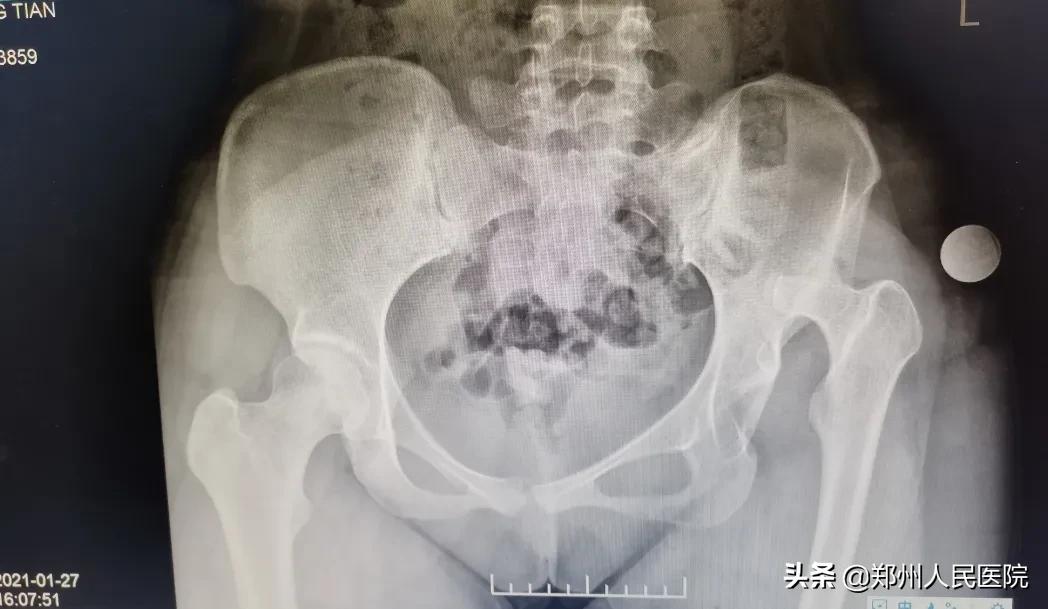

骨科三病区主任医师尹万乐为其查体后发现,文文患肢肌肉萎缩严重、双下肢粗细不一、长短不一、患肢缩短约6cm,骨质发育异常,髋关节磨损加重。

由于文文的髋关节发育不良,且髋关节磨损加重,建议其进行髋关节置换手术。

术前

“患者的情况已经不适合截骨手术,也就是保髋治疗。需要进行髋关节置换,放进一个人工的髋臼杯,再将股骨颈、磨坏的股骨头截掉,换上人工的股骨柄和股骨头,这样就形成了一个新的人工髋关节。通过手术可以解除患者髋关节的疼痛、改善走路一瘸一拐的症状。”尹万乐主任医师告诉小编。